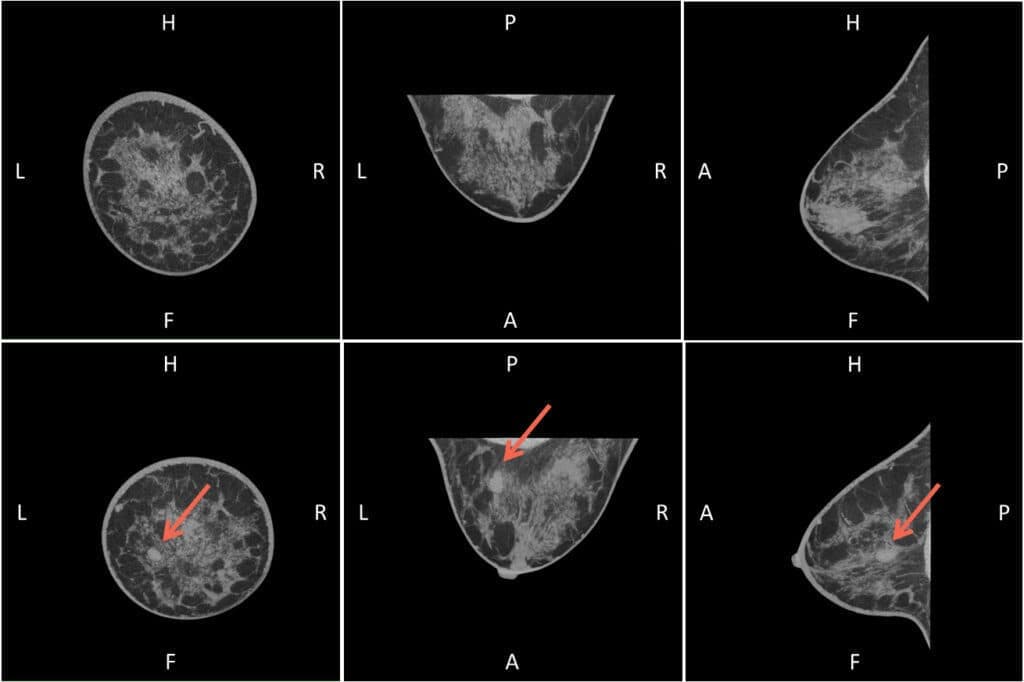

臨床症例

「nu:view の症例集をご参照ください。

本ページでは、nu:view による画像診断の有用性を示す代表的な臨床症例を掲載しております。」

また、乳房圧迫を伴わないスキャン方式により、患者の快適性にも配慮されています。単一スキャンにより、女性乳房の全体像を真の3D画像として重ね合わせなく再構成でき、軟部組織の識別能にも優れています。